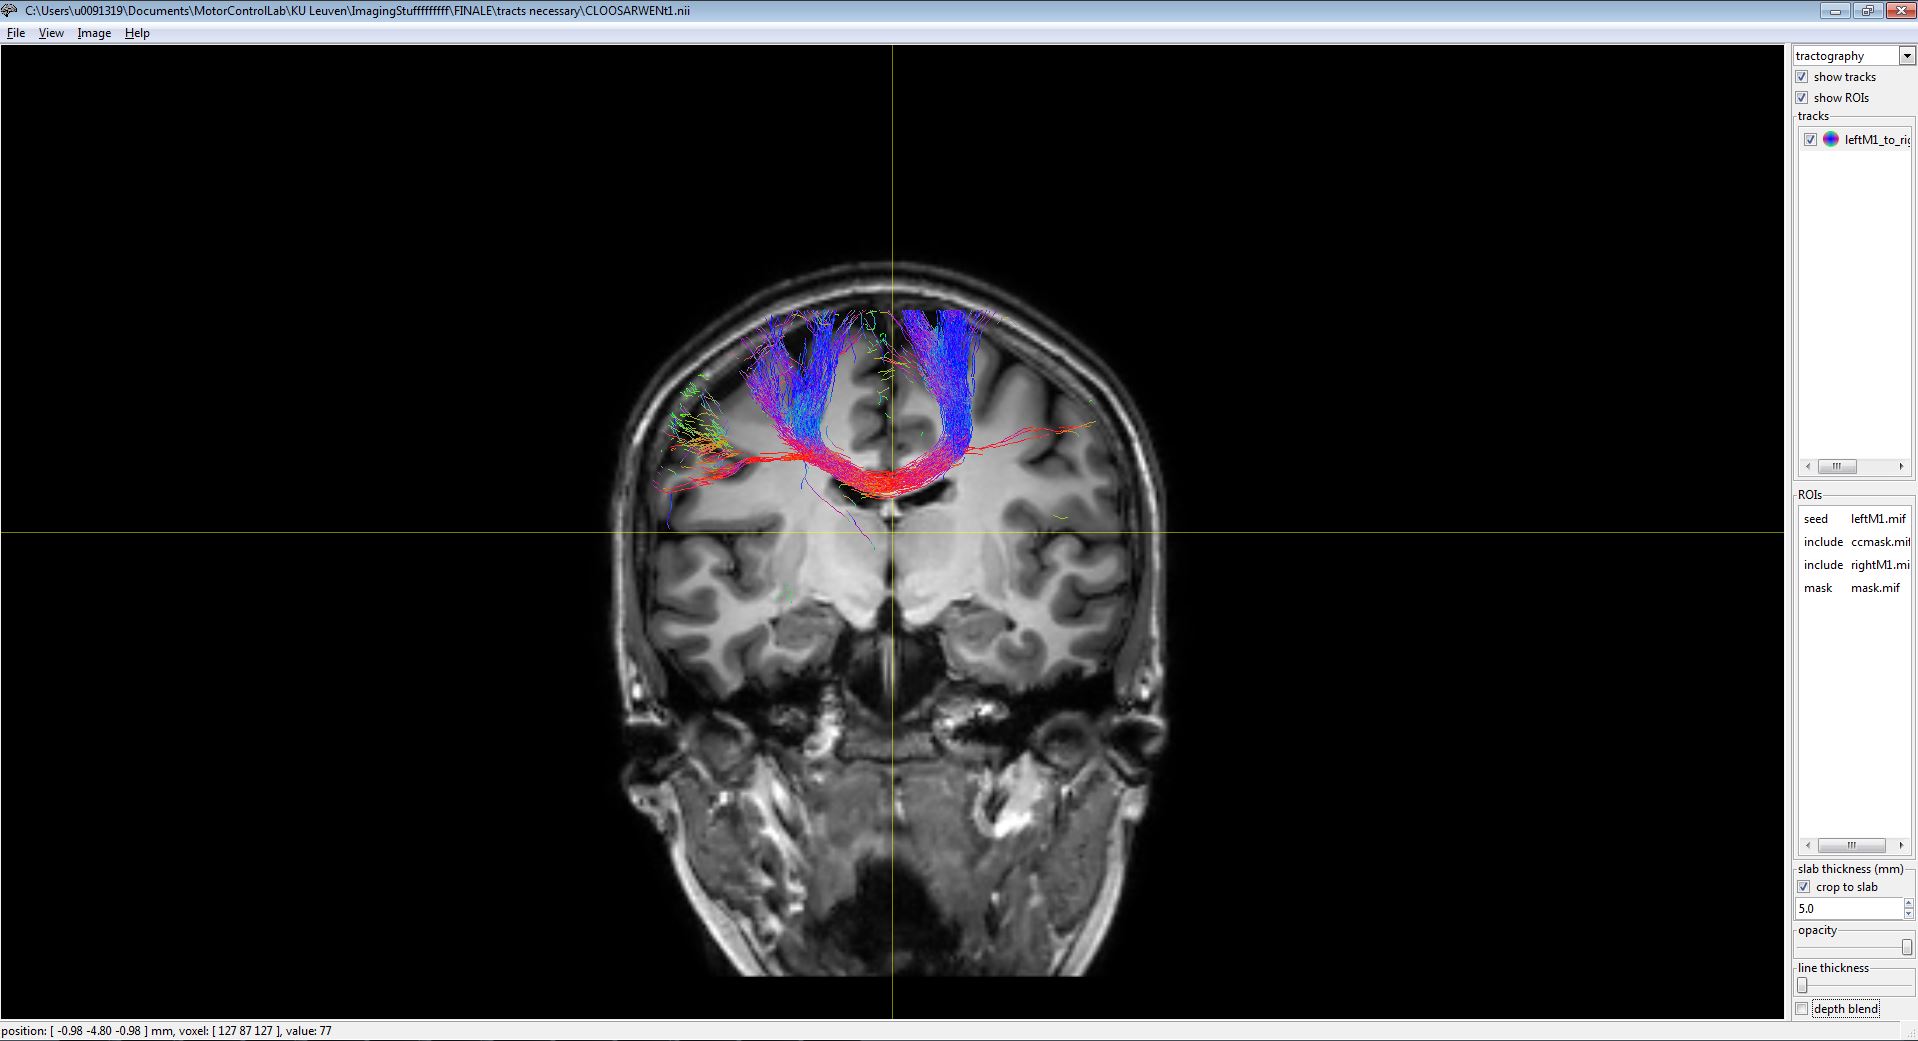

But somehow our tracts doesn't align with the individual T1 image (please see attached "m1-m1tckWithT1FiberNav.JPG"), though it does in Mrview (please see attached "m1-m1tckWithT1mrtrix.JPG").

Name: m1-m1tckWithT1mrtrix.JPG

Desc: m1-m1tckWithT1mrtrix.JPG